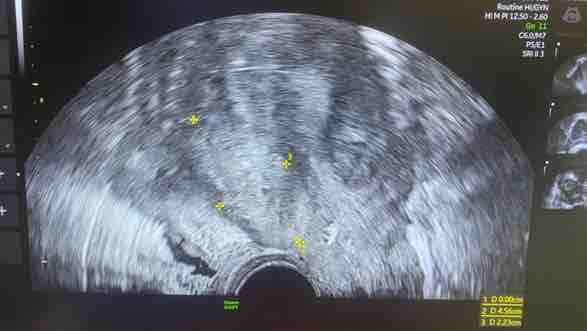

Ecosonografía transvaginal: Se visualiza útero en AVF, Heterogéneo de aspecto adenomiotico, en cara anterior de útero adenomioma mide 4,56 x 2,23 cm y en cara posterior se visualiza a nivel de istmo mioma de pequeño volumen, Ovario derecho se visualiza tumoración compatible luteoma, a nivel se unión rectosigmoidea se observa placa endometriosica que mide 2,22x 0,8 cm, signo de slicing negativo, Torus y ambos ligamentos uterosacros dolorosos a la exploración.

Susana, es mi prima, una joven de 32 años de edad, quien después de pasar mucho tiempo con fuertes dolores pélvicos hipogastrio de moderada intensidad, el cual no mejora con analgésicos-antiflamatorios, así mismo sangrado uterino irregular, maneja escala del dolor según funciones pélvicas: Dispareunia: 10/10pts, Disquecia: 10/10 pts, Dispareunia: 9/10 pts, Disuria: 10/10 pts. e intolerancia a los alimentos, el cual ha deteriorado su calidad de vida y actividades cotidianas. Le han descubierto, visualizando el útero en AVF, el cual es Heterogéneo de aspecto adenomiotico, en cara anterior de útero adenomioma mide 4,56 x 2,23 cm y en cara posterior se visualiza a nivel de istmo mioma de pequeño volumen, Ovario derecho se visualiza tumoración compatible luteoma, a nivel se unión rectosigmoidea se observa placa endometriosica que mide 2,22x 0,8 cm, signo de slicing negativo, Torus y ambos ligamentos uterosacros dolorosos a la exploración.